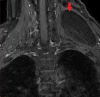

Figure 1. MRI Scan (Coronal)

Figure 2